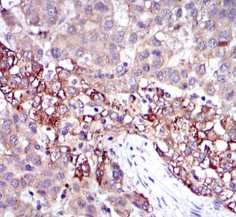

IHC    1/200 - 1/1000